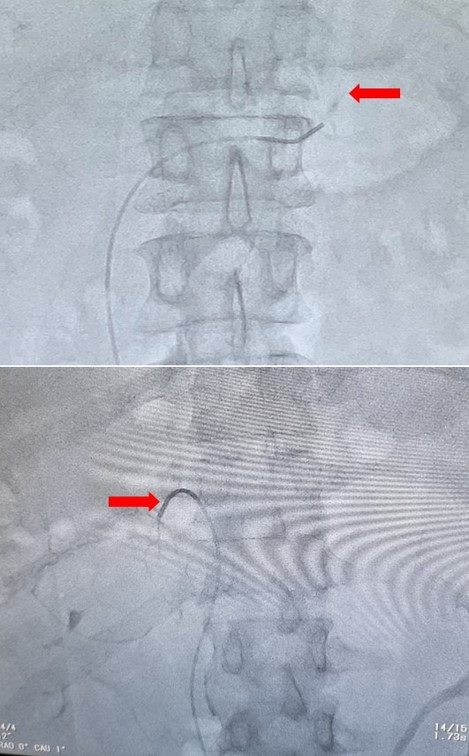

AVS被公认是原醛症分型诊断的“金标准”,是在DSA引导下,将导管插入双侧肾上腺静脉并抽血,通过检测血液醛固酮水平,来确定病患侧,为手术根治高血压提供指导。

红色箭头分别代表左右肾上腺静脉